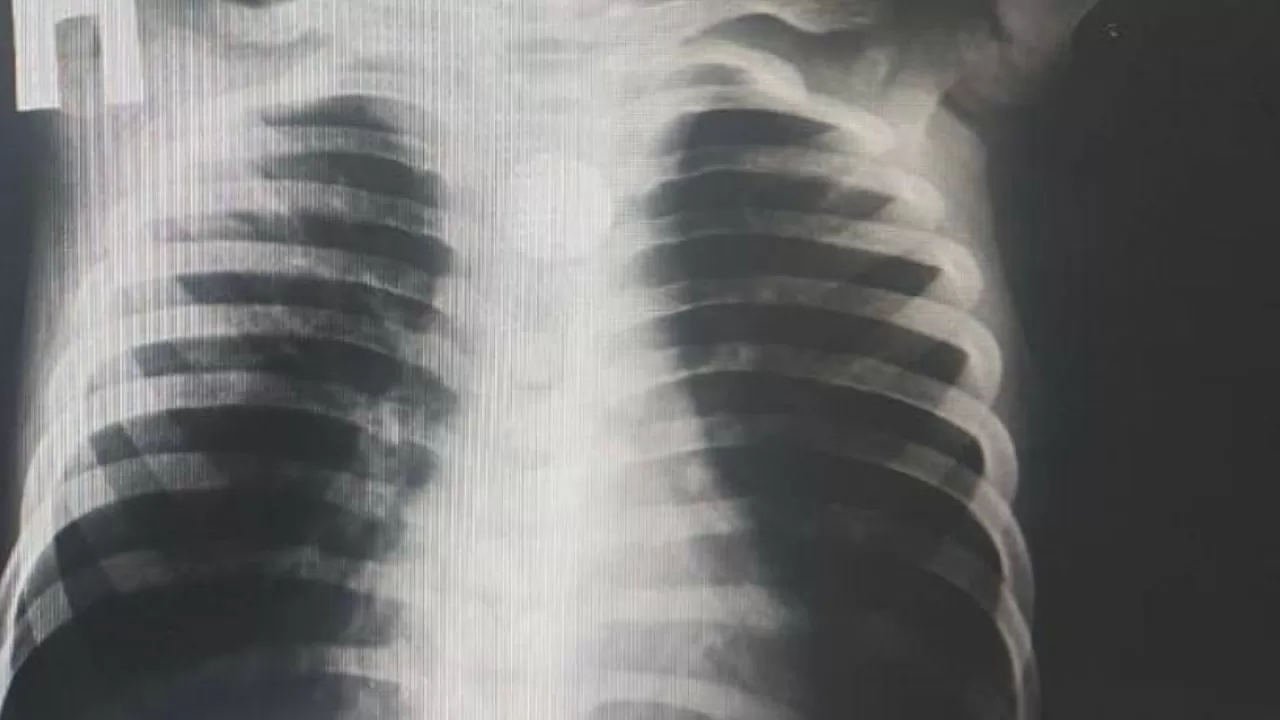

Анасының айтуынша, бала тамақ ішкеннен кейін жөтеліп, жүрегі айнып, сілекейі көп бөлінген. Аудандық орталық ауруханада жасалған рентгенологиялық тексеру кезінде өңешінде дөңгелек пішінді металл зат – батарейка анықталған. Науқас шұғыл түрде жедел жәрдеммен Түркістан облыстық балалар ауруханасына жеткізілді.

Қабылдау бөлімінде хирургтер мен эндоскопистер бірлесіп тексеру жүргізіп, қосымша зерттеулер жасады. Рентген нәтижесінде бөгде заттың өңештің жоғары үштен бір бөлігінде орналасқаны расталды. Баланы аман алып қалу үшін хирургтер шұғыл ота жасап, бөгде затты алып шықты.